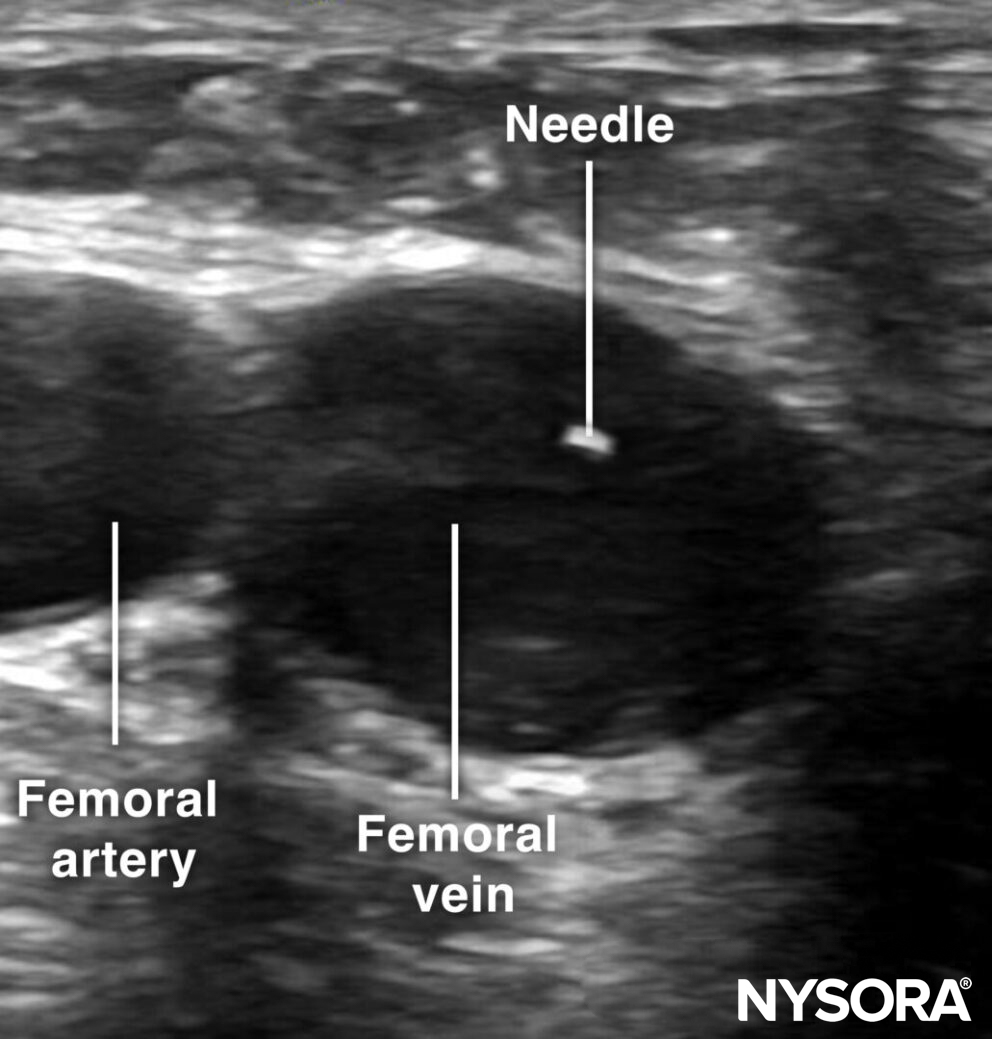

The femoral vein is approached just distal to the inguinal ligament by an out-of-plane technique. Use the creep technique to follow the needle tip at all times.

Out-of-plane cannulation of the femoral vein.